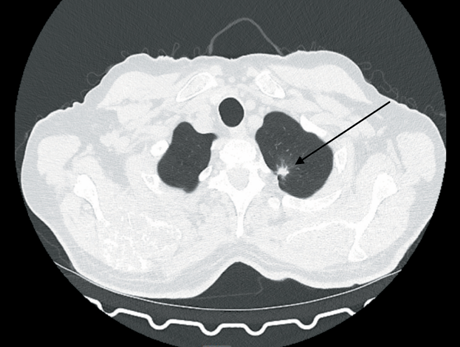

1. Рис. 1. МСКТ органов грудной полости (18.10.22): образо вание S1 левого легкого после 4 циклов терапии по схеме: атезолизумаб + бевацизумаб + карбоплатин + паклитаксел. В S1 легкого – образование с лучистыми тяжистыми контурами, размерами 10×11×8 мм (ранее 7×12×9 мм). Примечание: рисунок выполнен авторами